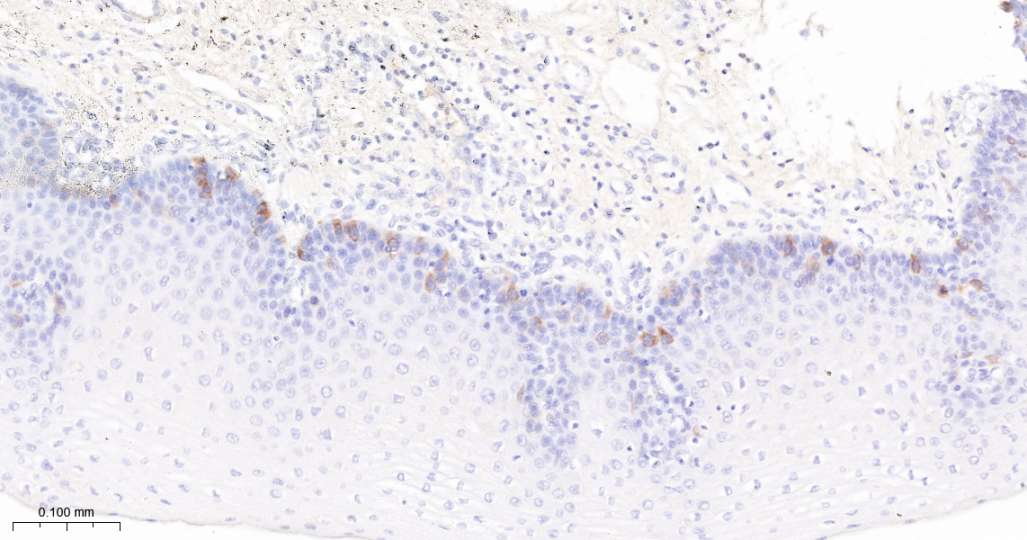

Immunohistochemical analysis of paraffin embedded Human brain tissue slide using IHC0690H (Human Cyclin B1 Kit).

Immunohistochemical analysis of paraffin embedded Human colon cancer tissue slide using IHC0690H (Human Cyclin B1 Kit).

Immunohistochemical analysis of paraffin embedded Human tonsil tissue slide using IHC0690H (Human Cyclin B1 Kit).

Immunohistochemical analysis of paraffin embedded Human thymus tissue slide using IHC0690H (Human Cyclin B1 Kit).

Immunohistochemical analysis of paraffin embedded Human esophagus tissue slide using IHC0690H (Human Cyclin B1 Kit).

Immunohistochemical analysis of paraffin embedded Human breast cancer tissue slide using IHC0690H (Human Cyclin B1 Kit).